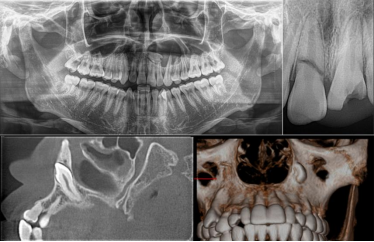

在牙体治疗中,影像学检查常用的是:X线片(根尖片,曲面体层片)、锥形束计算机断层扫描(CBCT)。通过X线片我们可以明确患牙、病变位置和范围,了解牙根及根管的数量、位置、大小和形态,评价根管治疗的质量及疗效。

通过CBCT我们可以更早期的检测根尖周病变的真实大小、范围、性质、位置及颌骨的骨质变化,更准确的评估根折、根管解剖结构以及颌骨的病变。